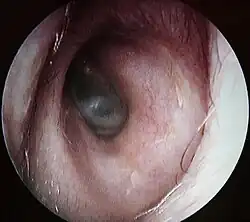

Conduit auditif externe gauche, au fond le tympan